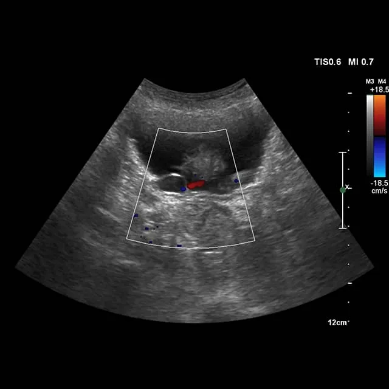

Controllo di Qualità sugli Ecografi

Come Assicurare l'Efficienza e la Precisione degli Esami Medici

Il controllo di qualità sugli ecografi è una pratica fondamentale per garantire l’affidabilità e l’accuratezza degli esami diagnostici. La qualità degli ecografi influisce direttamente sulla capacità di ottenere immagini chiare e precise, che sono cruciali per la diagnosi e il trattamento dei pazienti.

Il controllo di qualità ecografico si riferisce a una serie di procedure sistematiche che garantiscono il funzionamento corretto degli ecografi. Questi strumenti sono essenziali in medicina per eseguire ecografie, che consentono di visualizzare organi, tessuti e strutture interne senza l’uso di radiazioni. Gli ecografi possono essere utilizzati per una varietà di esami, tra cui ecografie addominali, ecografie cardiache e ecografie ostetriche.